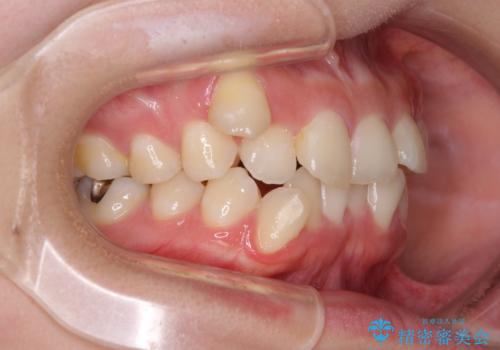

八重歯の抜歯矯正 補助装置とワイヤーを併用したインビザライン矯正治療

- 八重歯と上顎正中のズレを気にして来院された患者様です。

インビザラインによる矯正治療を希望されたため、八重歯改善のための抜歯矯正部分や上顎正中の大幅に位置移動は、補助装置やワイヤー矯正を併用し、その後はインビザラインにて行うこととしました。